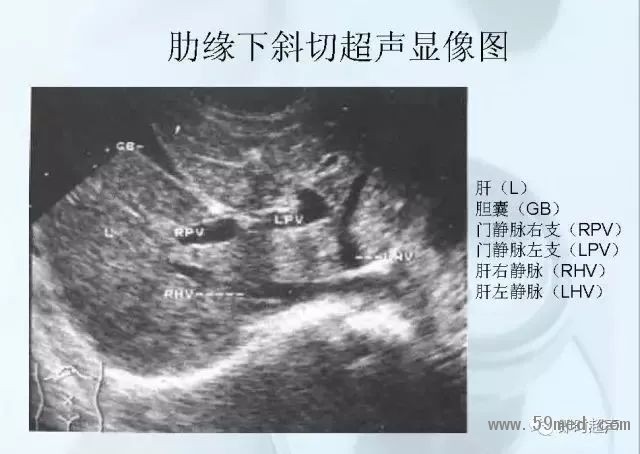

新聞中心 收藏!正常B超解剖圖譜,超實用!